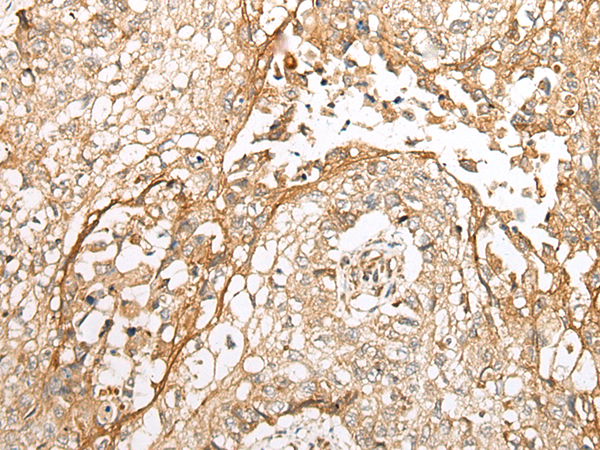

分类: 科研抗体货号: P02361别名: RNTRE; TRE2NL; USP6NL-IT1应用: WB,IHC反应种属: Human